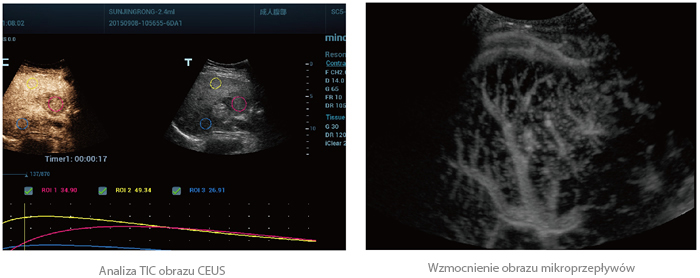

UWN+ Obrazowanie z użyciem środków kontrastujących

UWN+(Nieliniowa technologia Ultra-Wideband) CEUS umożliwia systemowi Resona 7 odbieranie i wykorzystywanie sygnałów drugiej harmonicznej i nieliniowych sygnałów podstawowych, generując znacznie ulepszone obrazy CEUS. Skutkuje to większą czułością mniejszych sygnałów i dłuższym czasem działania środka kontrastującego przy niskim MI.

20180920133729_2346